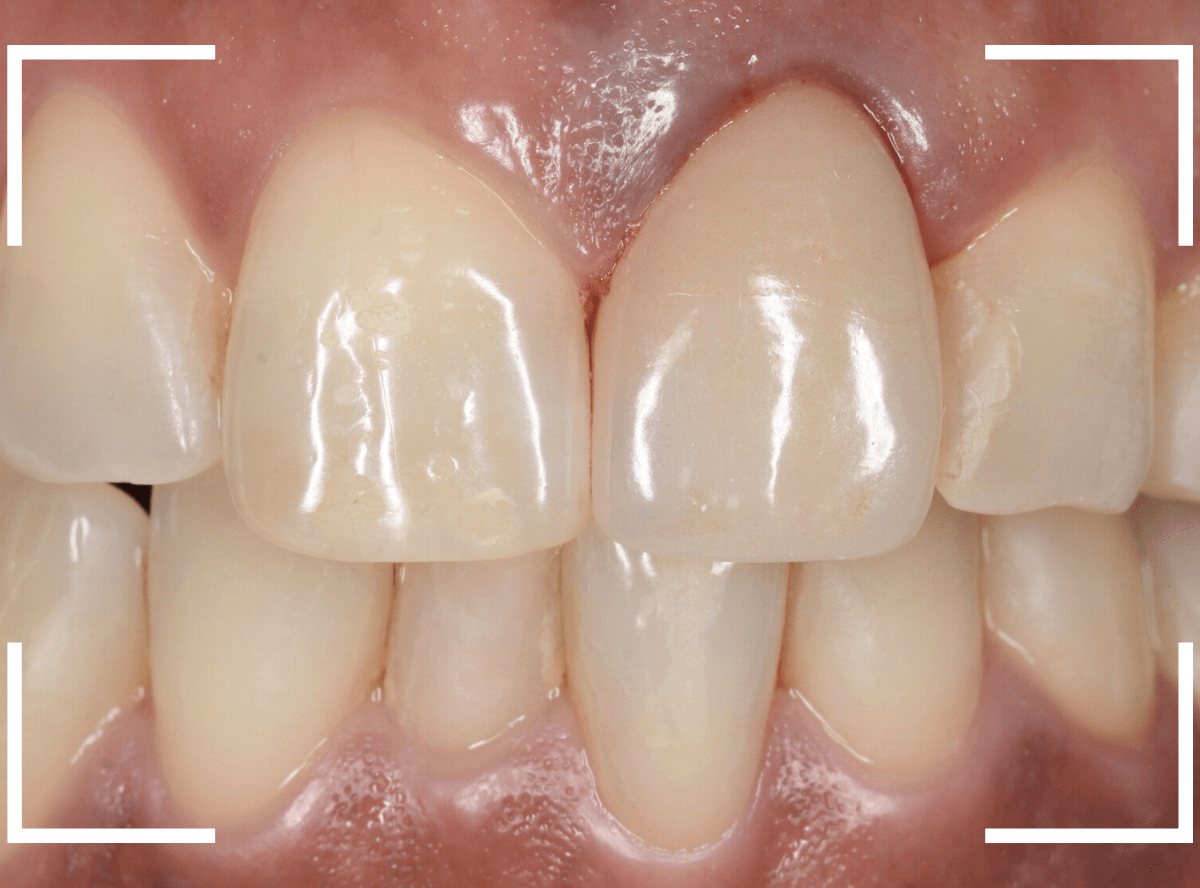

歯肉の治療がひと段落したところで、ジルコニア・セラミックで再製しました。

治療前と治療後の比較、前から見たところです。

患者さんにも満足いただけまして、ホッとしました。

裏側の歯肉も綺麗に治りました。

セラミックの表面はつるつるしていますので、歯周病の原因になるプラークがたまりづらく、治療後の経過も期待できます。